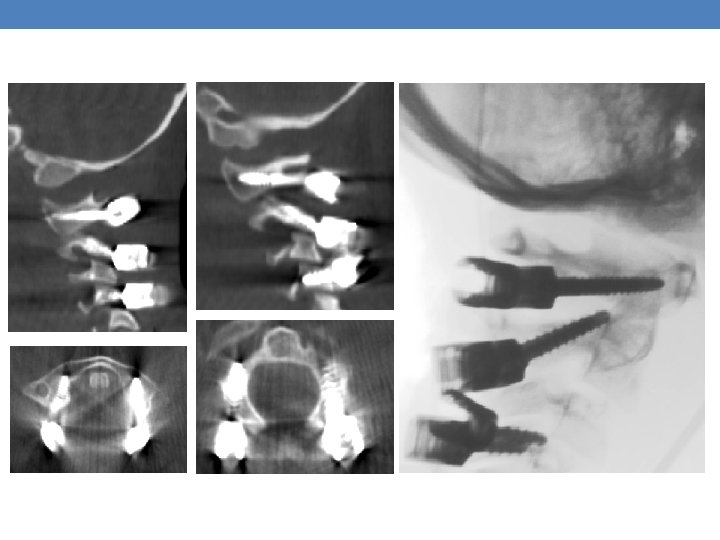

Case 1 A 6 -year-old female with no prior medical history was brought to the emergency room after a high energy car accident, complaining: • Paraplegia • Weakness (0/5) of the right upper limb • Severe neck pain • Respiratory distress The imaging showed an Atlanto-Occipital Dissociation

C 1, C 2 fixation with Goel. Harms technique and C 4 transarticular screw insertion